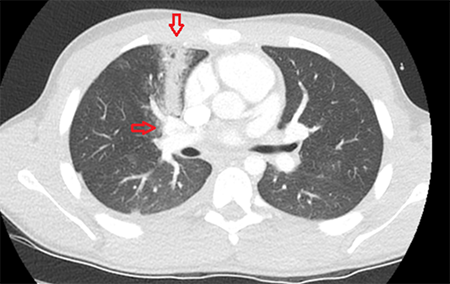

A focused assessment with sonography for trauma exam (Figure 2) was performed and showed a foreign body inside the left ventricle moving along with the ventricular wall contraction with no pericardial fluid. Hematocrit was normal.

Figure 2. Cardiac window showing foreign body inside the heart with no pericardial effusion.